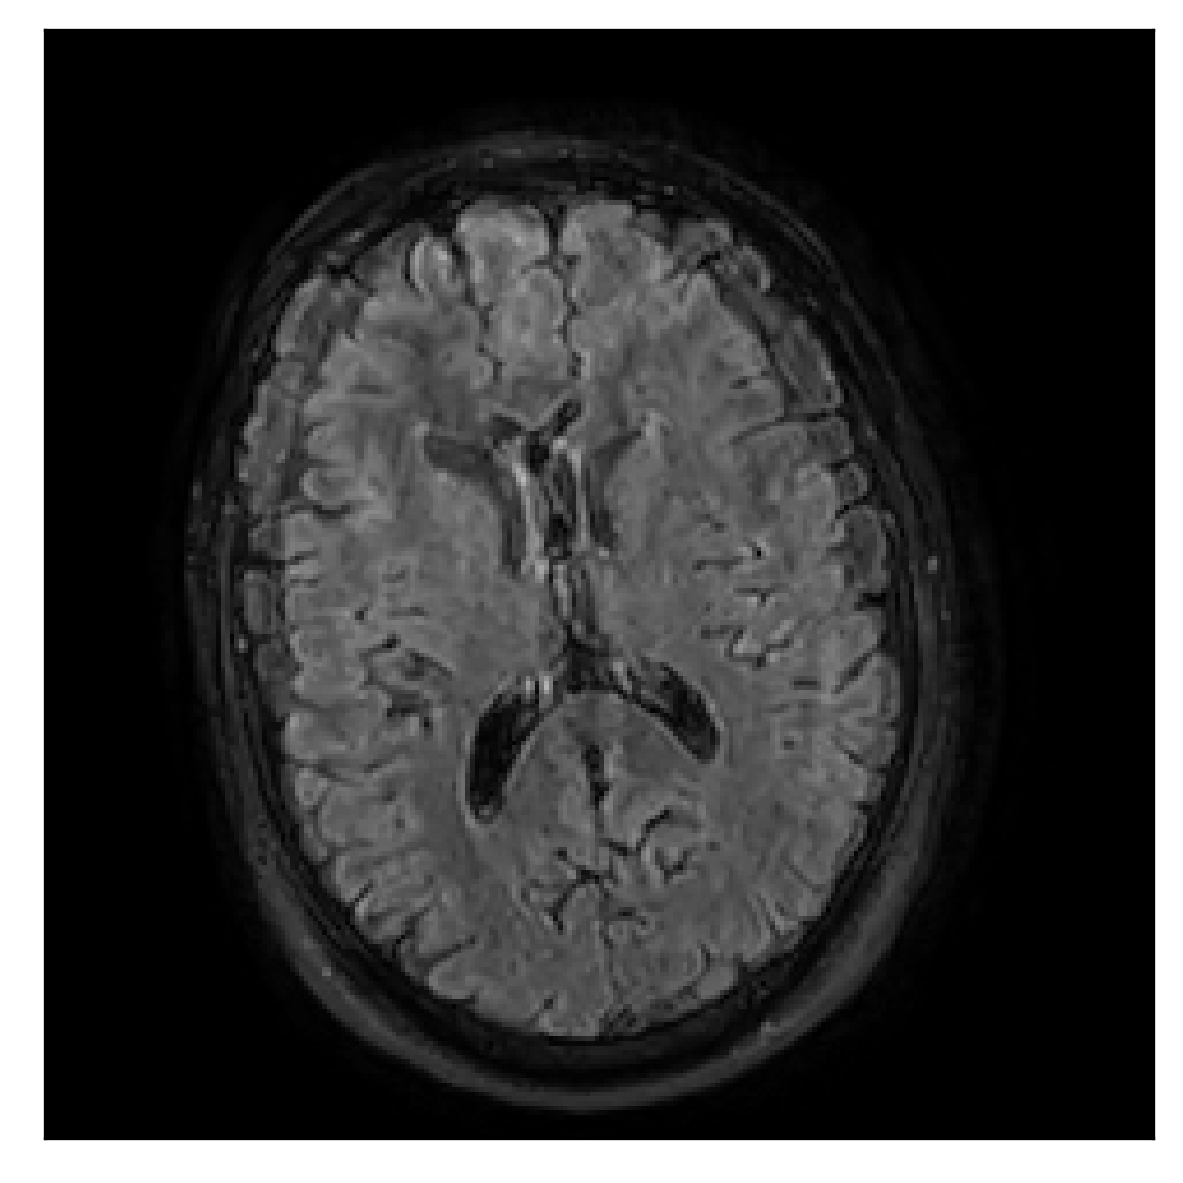

We consider three levels of motion corruption: (i) the volunteer moves once, (ii) the volunteer moves twice, and (iii) the volunteer moves five times. The volunteer is instructed to change its head position every time it is prompted to do so, and maintain that position in between instructions. We use T2-FLAIR-weighted contrasts as corrupted scans, with T1-weighted contrast as a reference (see Table 1 for further details). The corrupted acquisition employs randomized sampling.

4.1 Experiment 1: robustness test

We gather the results for the robustness test described in Section 3.1 (volunteer 1) in Figures 2, 4, and 6 for motion corruption mechanisms associated to one, two, and five changes of position, respectively. Furthermore, we juxtapose the corrected images with varying degrees of corruption in Figure 8. We observe that the proposed method consistently ameliorates the corrupted scan. The quality indexes based on PSNR and SSIM show only a modest decrease in correction quality as a function of motion complexity (Figure 8).

| Section 3.1, Figure 2 | Sagittal | 23.94 | 27.95 | 0.7068 | 0.7936 |

| Coronal | 26.66 | 29.82 | 0.7653 | 0.8332 | |

| Axial | 25.40 | 30.16 | 0.7616 | 0.8490 | |

| Section 3.1, Figure 2 | T2-FLAIR | Completely corrected | Some blurring | No additional artifacts | Good grey white matter differentiation |